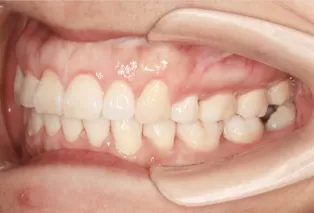

Intraoral photos